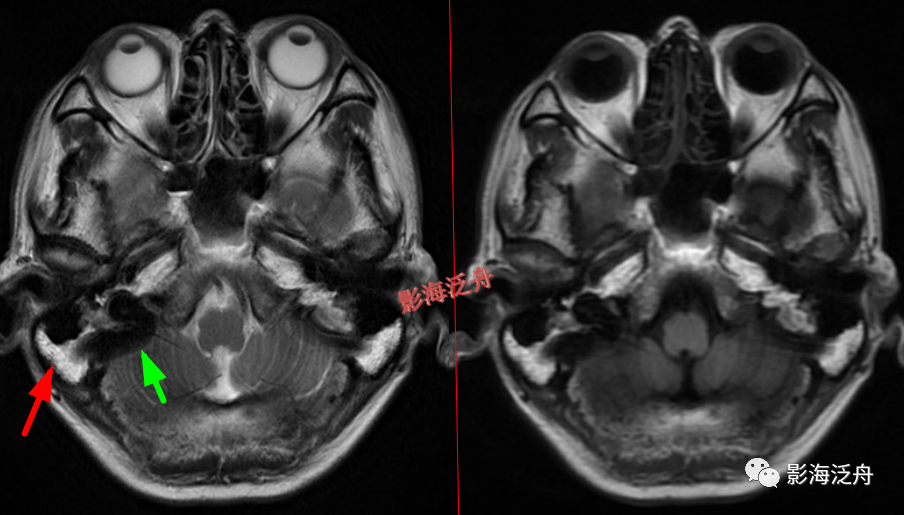

左侧乳突炎(红箭),右侧乳突气化良好,不含炎症,在mr上呈无信号(慢箭